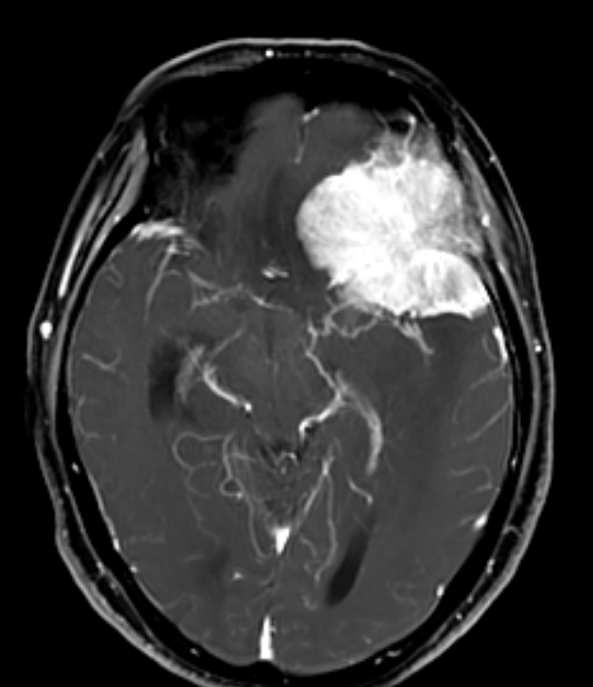

73岁的李奶奶,因头痛、痴呆半年入院。检查发现,其左侧蝶骨嵴位置生长了一个6厘米的肿瘤。这个肿瘤如同生长的藤蔓,将大脑中动脉及其主要分支紧紧包裹缠绕,并已引起脑疝,病情危殆。

术中,黎建先主任在高倍手术显微镜下,以超凡的耐心和稳定如磐的双手,像整理最精细的丝线一般,将至关重要的动脉血管一根根从肿瘤组织中小心翼翼地分离、保护出来,最终既实现了肿瘤的全切,又完好保留了患者宝贵的神经功能。